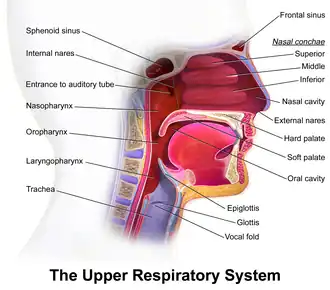

In humans, the pharynx is part of the digestive system and the conducting zone of the respiratory system. (The conducting zone—which also includes the nostrils of the nose, the larynx, trachea, bronchi, and bronchioles—filters, warms, and moistens air and conducts it into the lungs).[1] The human pharynx is conventionally divided into three sections: the nasopharynx, oropharynx, and laryngopharynx (hypopharynx).

Nasopharynx

The upper portion of the pharynx, the nasopharynx, extends from the base of the skull to the upper surface of the soft palate.[2] It includes the space between the internal nares and the soft palate and lies above the oral cavity. The adenoids, also known as the pharyngeal tonsils, are lymphoid tissue structures located in the posterior wall of the nasopharynx. Waldeyer's tonsillar ring is an annular arrangement of lymphoid tissue in both the nasopharynx and oropharynx. The nasopharynx is lined by respiratory epithelium that is pseudostratified, columnar, and ciliated.

Polyps or mucus can obstruct the nasopharynx, as can congestion due to an upper respiratory infection. The auditory tube, which connects the middle ear to the pharynx, opens into the nasopharynx at the pharyngeal opening of the auditory tube. The opening and closing of the auditory tubes serves to equalize the barometric pressure in the middle ear with that of the ambient atmosphere.

Oropharynx

Laryngopharynx

The laryngopharynx, (Latin: pars laryngea pharyngis), also known as hypopharynx, is the caudal part of the pharynx; it is the part of the throat that connects to the esophagus. It lies inferior to the epiglottis and extends to the location where this common pathway diverges into the respiratory (laryngeal) and digestive (esophageal) pathways. At that point, the laryngopharynx is continuous with the esophagus posteriorly. The esophagus conducts food and fluids to the stomach; air enters the larynx anteriorly. During swallowing, food has the "right of way", and air passage temporarily stops. Corresponding roughly to the area located between the 4th and 6th cervical vertebrae, the superior boundary of the laryngopharynx is at the level of the hyoid bone. The laryngopharynx includes three major sites: the pyriform sinus, postcricoid area, and the posterior pharyngeal wall. Like the oropharynx above it, the laryngopharynx serves as a passageway for food and air and is lined with a stratified squamous epithelium. It is innervated by the pharyngeal plexus and by the recurrent laryngeal nerve.

The nasopharynx, oropharynx, and laryngopharynx or larynx can be seen clearly in this sagittal section of the head and neck.

The nasopharynx, oropharynx, and laryngopharynx or larynx can be seen clearly in this sagittal section of the head and neck.